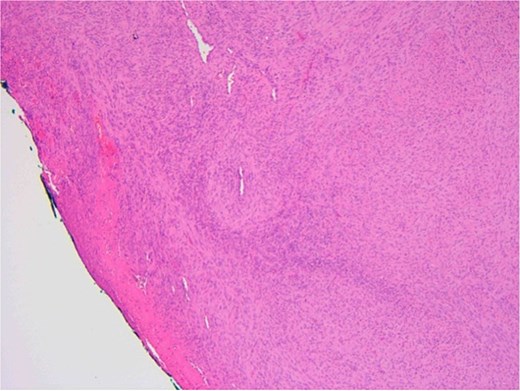

The patient underwent a biopsy of the lesion. Histopathological analysis revealed spindle cell proliferation arranged in a fascicular growth pattern, dilated hemangiopericytoma-like vessels, and a central myeloid nodule. Immunohistochemical staining was positive for smooth muscle actin (SMA), with no evidence of cellular atypia (Figs 5–7).

SMA immunostain showing diffuse positivity in spindle cells and highlighting myoid nodules.